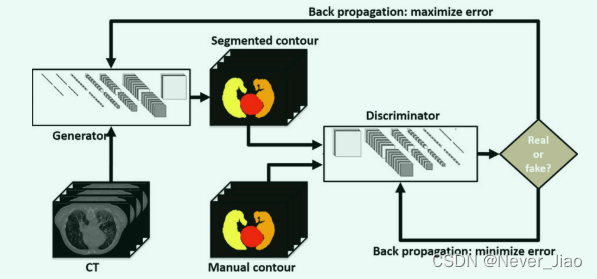

由于 CT 图像的对比度限制,手动轮廓,尤其是器官边界周围的轮廓,容易出现观察者间的差异。由于手动轮廓作为分割网络的目标,轮廓可变性导致端到端网络模型(例如 U-Net)的不稳定。 GAN 模型将端到端网络作为生成器,并通过判别器引入额外的判断,以帮助生成器找到最佳解决方案。如图2所示,基于GAN的分割模型由一个生成器网络和一个鉴别器网络组成。这两个网络在零和博弈框架下依次进行了优化。生成器的训练目标是增加鉴别网络的判断误差(即,通过产生与手动轮廓难以区分的新的分割轮廓来“愚弄”鉴别器)。鉴别器的训练目标是减少鉴别器网络的判断错误,增强区分真假的能力。在两个网络中都应用了反向传播,因此生成器产生了更逼真的分割,而鉴别器变得更加熟练地将分割的轮廓与手动轮廓进行区分。因此,我们在算法中应用了这个众所周知的GAN网络。

Fig.2 一个示例说明了生成对抗网络的过程。